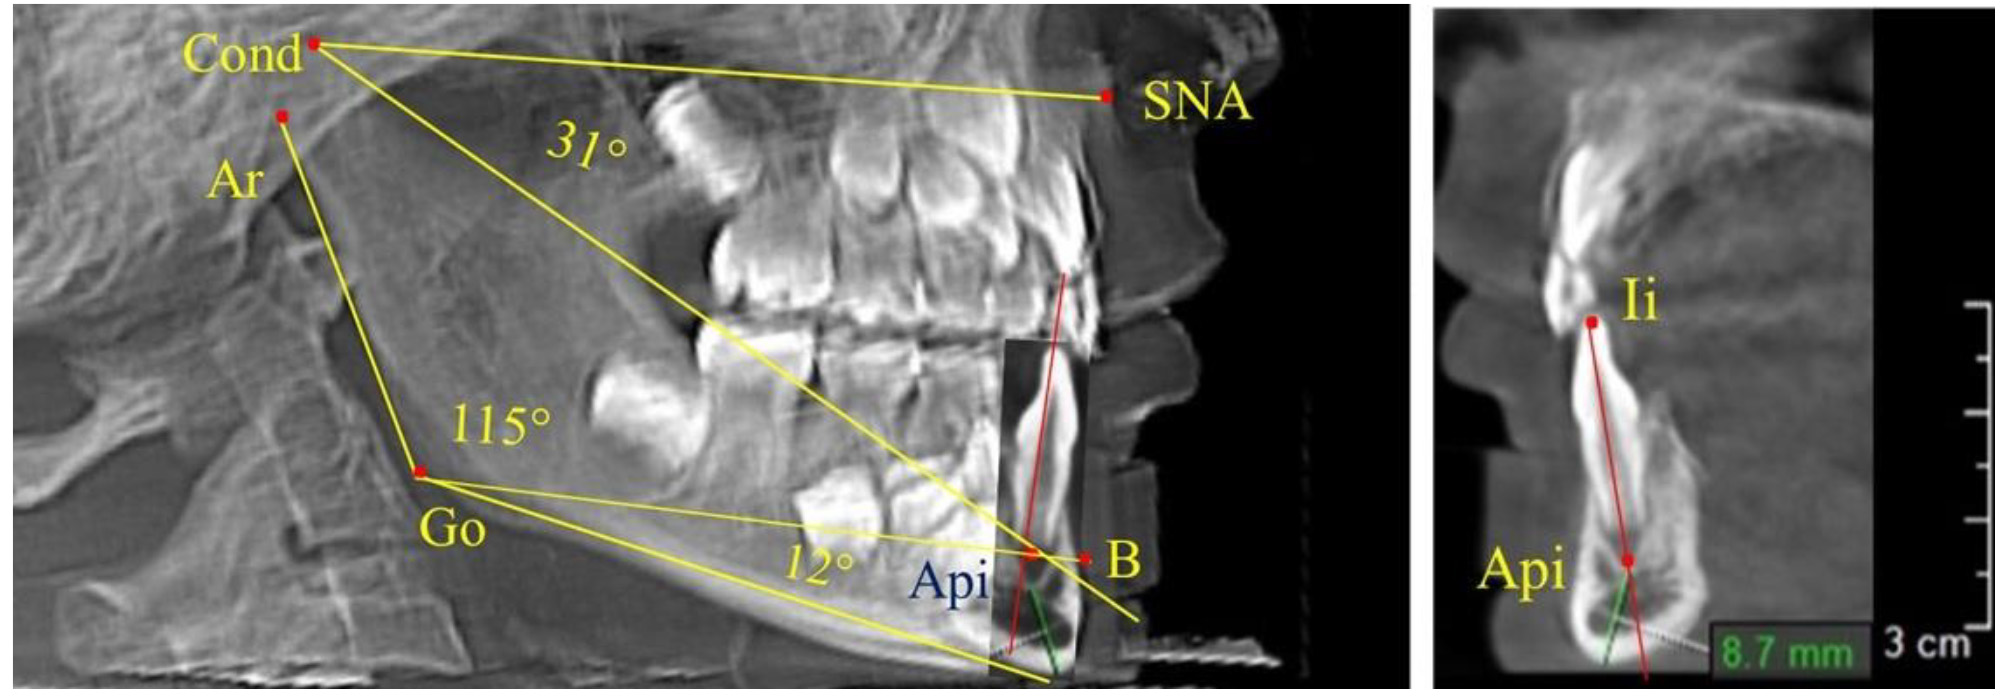

Через апикальную точку нижнего резца от суставной точки проводили линию Cond-Api, которая с линией Cond-SNA образовывала угол гнатический части лица SNA-Cond-Api, используемый для оценки ее основных параметров.

Кроме того, угол нижней челюсти Ar-Go-Me линией Go-Api делили на две составляющие. Верхняя часть угла Ar-Go-Api определяла значение альвеолярного нижнечелюстного угла, а угол Api-Go-Me определял особенности части тела нижней челюсти (рис. 1).

Рис. 1. Расположение реперных точек (а) и линий (б) для оценки угловых параметров гнатической части телерентгенограммы

Особенность анализа телерентгенограммы в периоде сменного прикуса заключалась в том, что наслоение зачатков постоянных зубов затрудняло определение апикальной точки нижнего резца. В подобных случаях использовали метод совмещенного анализа телерентгенограммы с фрагментом томограммы, на котором, также как и на телерентгенограмме, определяли положение резцовой и апикальной точек с построением условной вертикали, которая служила ориентиром для совмещения фрагментов (рис. 2).

Рис. 2. Особенности совмещения телерентгенограммы с фрагментом томограммы в сменном прикусе